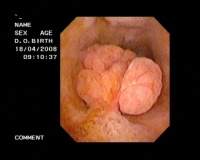

3.内镜超声(endoscopic ultrasonography,EUS) 即经内镜超声扫描,是将超声微小探头安置在内镜顶端,探头为高频,将内镜插入消化道,进入十二指肠壶腹后此探头更接近胆囊,可排除肠气干扰或胆汁黏稠度等影响。EUS可将胆囊壁分为3层,内层为高回声黏膜及黏膜下层,中层为低回声的肌纤维层,外层为高回声的浆膜下层及浆膜层。如为息肉样病变可见清晰的3层囊壁,而胆囊癌则囊壁的3层结构有不同程度的浸润破坏。早期胆囊癌绝大多数是在结石和息肉等病变的掩盖下发展的,早期缺乏特征性声像图表现,鉴别困难。而EUS检查观察息肉样病变与胆囊壁之关系,有助于鉴别诊断。朱燕陵等回顾分析了103例非结石性胆囊病变EUS检查结果并与体表超声及手术后病理进行比较,EUS检查诊断正确率为75%,体表超声为41.4%,EUS对胆囊息肉、胆囊癌、胆囊腺肌瘤诊断符合率为100%,体表超声为55.6%。Sugiyama认为内镜超声(EUS)比BUS更准确,提供的图像也更清晰。因194例PLG中,EUS判断的136例非肿瘤性病变平均随访2.6年均未发现肿瘤;而BUS判断的非肿瘤性病变中则有13%为肿瘤。EUS内层的回声方式为细小声点(tiny echonic spot)、声点聚集(aggregation of echogenic spot)、微小囊肿(microcyst)及彗星尾征(comet tailartifact)。如EUS证实既无细小声点与声点聚集,又无微小囊肿与彗星尾征时,应怀疑为腺瘤或癌肿。两者无法鉴别,除非已浸润至肝脏,但若为无蒂病变,则强烈提示为癌肿。结合组织学研究,一个细小声点表示一群含有胆固醇泡沫的组织细胞,而无回声区则为腺上皮增生。多个小囊肿和彗星尾征则分别为罗-阿窦增多和胆囊壁内结石所致。

目前的手术方法有传统手术、腹腔镜手术和保胆手术。传统手术的方法医学界普遍认为创伤大、恢复慢;目前使用得比较少。腹腔镜的方法是在病人的腹壁上做四个小切口,然后放入穿刺器械,通过从肚脐放入的腹腔镜可以观察得一目了然,可以进行很好的切除工作。 如果在有经验的医生操作下,则创伤小、恢复快。胆囊有消化和储藏胆汁的作用,一部分患者觉得切了可惜,可以采用保胆囊取息肉的方法,保胆手术在皮肤上打个小口,用纤维胆道镜进入胆囊,找到病理的部位,这种方法的优势在于保住了整个胆囊,而且可以做病理检查,看看息肉到底是恶性的还是良性的,如果是恶性的就同时处理,但这种方法开展的时间比较短,还有待临床的进一步观察。

(1)腺瘤:多为单发的有蒂息肉,外形可呈乳头状或非乳头状,恶变率约30%,癌变机会与腺瘤大小呈正相关。1998年国外学者观察良性胆囊息肉样病变时发现,其中94%直径<10mm,66%的患者年龄<60岁;而恶性胆囊息肉样病变88%直径>10mm,75%的患者年龄>60岁。研究认为,胆囊腺瘤的发病率很低,在10年内施行的12153例胆囊切除中,仅81例为胆囊息肉样病变,只占0.7%,而其中是腺瘤的仅为9.6%;而同期人群中发现胆囊癌225例,占1.85%,可见本病有癌变的可能性。

(2)腺癌:分为乳头型、结节型及浸润型。前两者为隆起性病变,直径约<20mm;而浸润型不属于胆囊息肉样病变,绝大多数直径>20mm。因此表现为胆囊息肉样病变的胆囊癌往往为早期,其中乳头型癌绝大多数限于黏膜和肌肉内,预后良好。